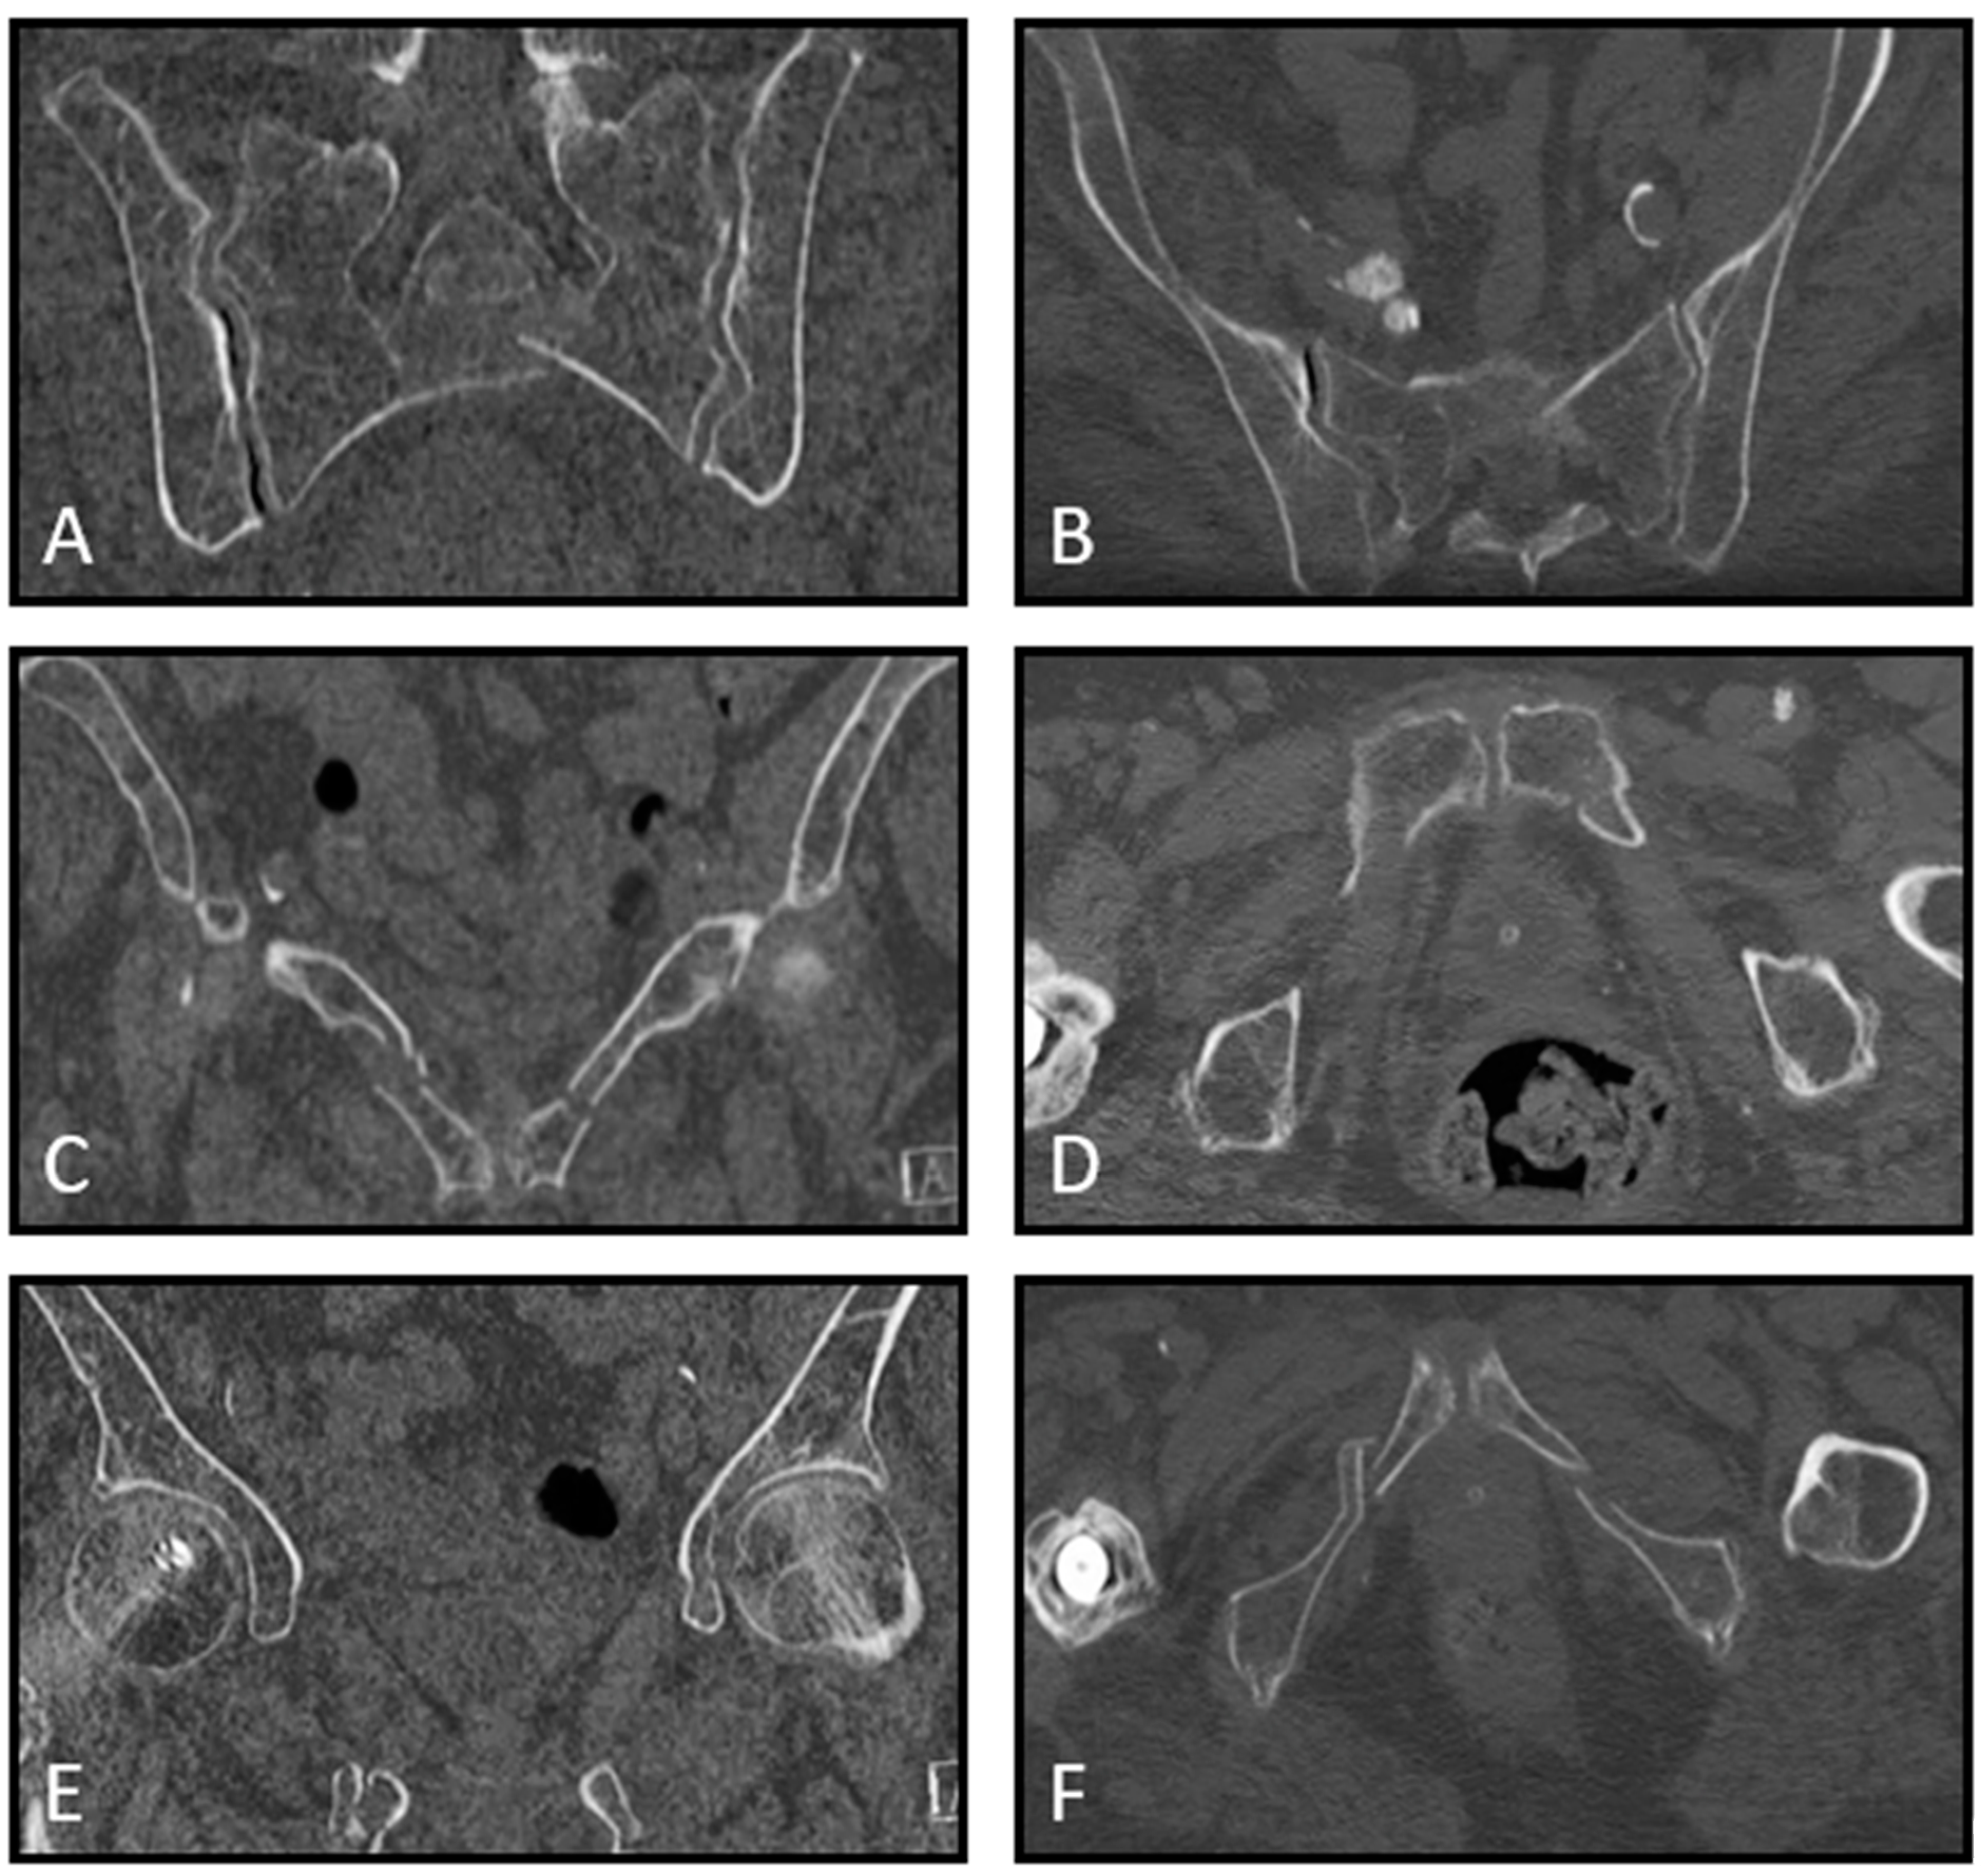

| 14. Mrs. C. is a 75-year-old, independently living ASA 2 patient. She fell on the street, and plain radiographic imaging showed a superior/inferior ramus fracture on the right side. She is discharged from the ER with oral painkillers. The patient comes back to your outpatient clinic after 14 days. She mobilizes with difficulty, sits in a wheelchair, walks with a four-wheel walker indoors, and uses Paracetamol and Diclofenac. A CT scan shows an LC1/FFP3c fracture. Do you think, based on this information, the patient is eligible for surgical fixation? | A. No, I do not think this is indicated and would have little impact on this patient’s outcome B. No, I think operative pelvic fixation would be too invasive for this patient C. Yes, if the patient has evident pelvic pain during a physical exam D. Yes, only if the pain did not decrease at 6 weeks follow-up E. Otherwise, namely: |

| 15. Mrs. D. is a 69-year-old, independently living ASA 3 patient with COPD Gold 3. She fell on the street, and plain radiographic imaging showed a superior/inferior ramus fracture on the right side. She is discharged from the ER with oral painkillers. The patient comes back to your outpatient clinic after 14 days. She mobilizes with difficulty, sits in a wheelchair, walks with a four-wheel walker indoors, and uses Paracetamol and Diclofenac. A CT scan shows an LC1/FFP3c fracture. Do you think, based on this information, the patient is eligible for surgical fixation? | A. No, I do not think this is indicated and would have little impact on this patient’s outcome B. No, I think operative pelvic fixation would be too invasive for this patient C. Yes, if the patient has evident pelvic pain during a physical exam D. Yes, only if the pain did not decrease at 6 weeks follow-up E. Otherwise, namely: |

| 16. Mrs. E is an 81-year-old ASA 3 patient. She fell on the street, and plain radiographic imaging showed a superior/inferior ramus fracture on the right side. She is admitted to the nursing ward and has difficulty turning in bed. Transfer from bed to toilet chair is possible. She uses Paracetamol, Diclofenac and Oxynorm. A CT scan shows an LC1/FFP3c fracture. Do you think, based on this information, the patient is eligible for surgical fixation? | A. No, I do not think this is indicated and would have little impact on this patient’s outcome B. No, I think operative pelvic fixation would be too invasive for this patient C. Yes, if the patient has evident pelvic pain during a physical exam D. Yes, only if the pain did not decrease at 6 weeks follow-up E. Otherwise, namely: |